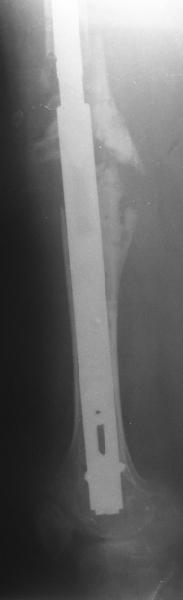

Female, rheumatoid, THA in 2003, car accident in 2006, failed plating. Nailing in Oct 2007. The nail is solid with hollow proximal part where the stem is docked. Last images are in 1 year after

nailing.

I heard from many european colleagues about anecdotal use of old hollow Kuntscher nails for that purpose. Prof. R.Schnettler (Germany) recently told about 57 cases. I have only 2 such cases done last year, both on cementless stem. This approach is very attractive by that we achieve the same goal - "new long stem" but much less invasive.